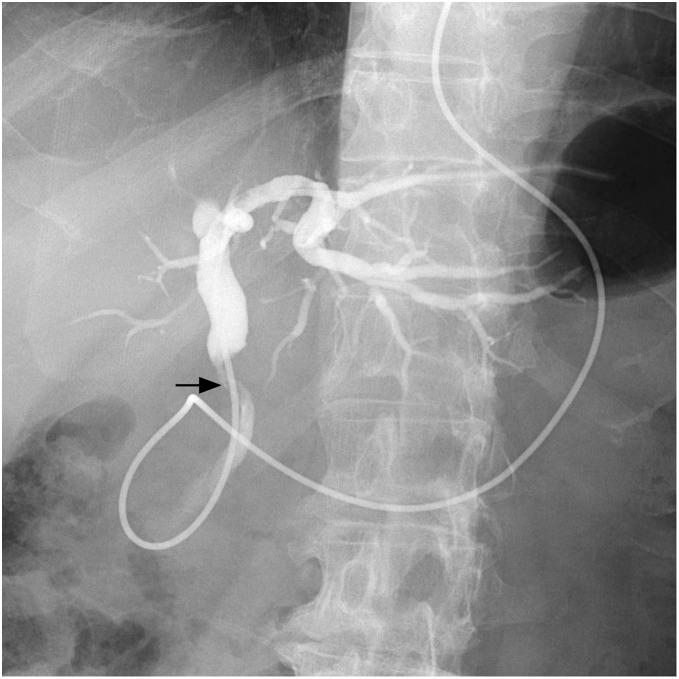

A 67-year-old man was referred to our hospital for evaluation of jaundice. Contrast-enhanced computed tomography revealed an enhanced tumor on the common bile duct. Endoscopic retrograde cholangiography showed bile duct stenosis due to a nodular tumor of the common bile duct. We performed subtotal stomach-preserving pancreaticoduodenectomy under diagnosing distal cholangiocarcinoma. The patient was discharged on the 23rd postoperative day. Macroscopic findings of the resected specimen showed a 27-mm nodular-infiltrating tumor at the middle bile duct and a 3-mm nodular tumor at the lower bile duct. The distance between the tumors was 10 mm. Pathological examination revealed that the larger tumor was primarily composed of poorly differentiated adenocarcinoma, with a moderately differentiated component at the periphery of the tumor. The smaller tumor was entirely composed of poorly differentiated adenocarcinoma, which was similar to the poorly differentiated component of the larger tumor. Additionally, microscopic lymphovascular infiltration was observed in the vicinity of both tumors. These two lesions were separated by nontumoral biliary epithelia without atypia. The results of immunohistochemical staining using CK7/20, MUC1/2, and p53 antibodies substantiated the homology of these tumors. These results suggested that the smaller tumor was synchronous intramural bile duct metastasis of distal cholangiocarcinoma rather than independent multiple lesions.

一名67岁男性因黄疸来我院就诊。增强计算机断层扫描显示胆总管上有一个强化肿瘤。内镜逆行胆管造影显示胆总管的结节状肿瘤导致胆管狭窄。我们在诊断为远端胆管癌的情况下进行了保留胃的胰十二指肠次全切除术。患者术后第23天出院。切除标本的宏观检查显示,在胆总管中部有一个27毫米的结节浸润性肿瘤,在胆总管下部有一个3毫米的结节状肿瘤。两个肿瘤之间的距离为10毫米。病理检查显示,较大的肿瘤主要由低分化腺癌组成,肿瘤周边有中分化成分。较小的肿瘤完全由低分化腺癌组成,与较大肿瘤的低分化成分相似。此外,在两个肿瘤附近均观察到微小淋巴管浸润。这两个病变被无异型性的非肿瘤性胆管上皮分隔开。使用CK7/20、MUC1/2和p53抗体进行免疫组化染色的结果证实了这些肿瘤的同源性。这些结果表明,较小的肿瘤是远端胆管癌的同步壁内胆管转移,而不是独立的多发病变。